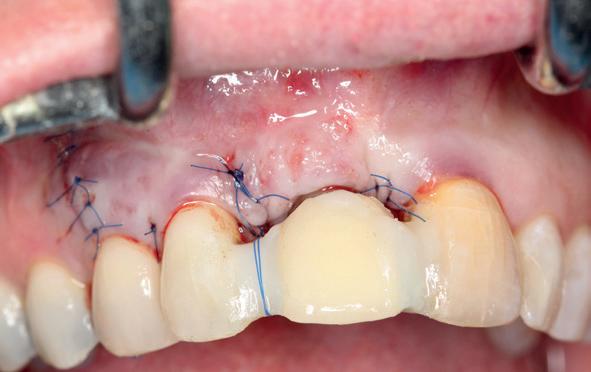

Er werd meer bekend over de gedragingen van het bot rond de “microgap” en daarmee kwam er meer begrip over hoe een implantaat goed te plaatsen in de esthetische zone. In het midden van de jaren negentig kwam daar de kennis bij hoe, op een verantwoorde manier en met behulp van guided-bone-regeneration, een implantaat in de esthetische zone te plaatsen (afbeelding 6-10).

Van vooral functionaliteit verschoof de indicatie naar esthetiek. De zachteweefselchirurgie en vaak voorbehandeling van zachte weefsels voor implantologie kreeg veel meer aandacht (afbeelding 11-14).